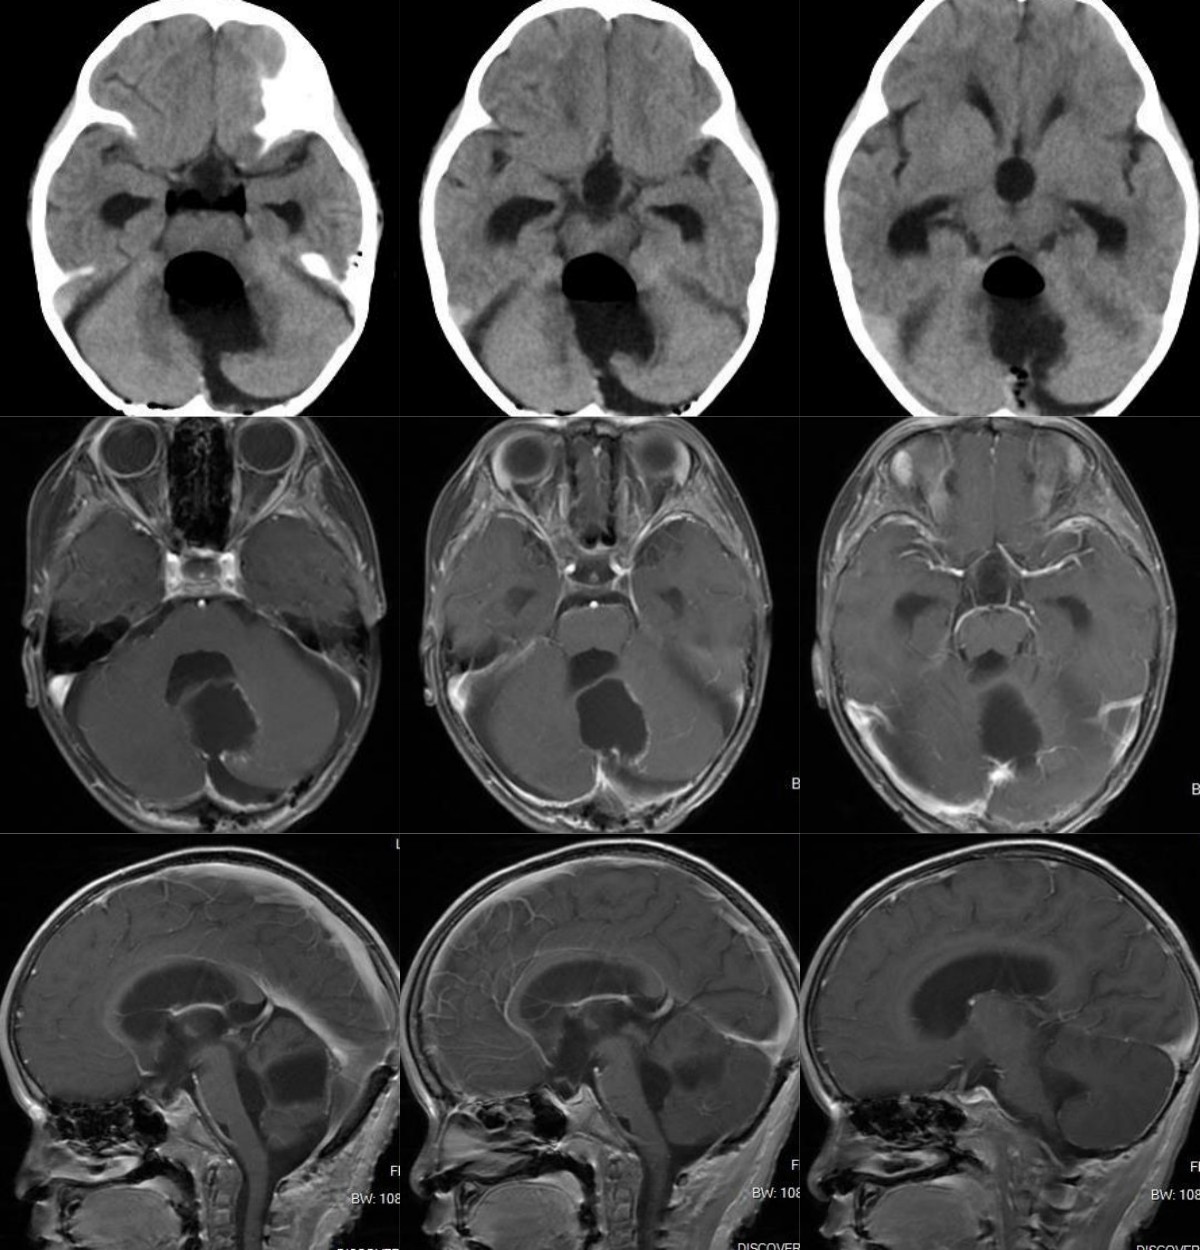

患儿高**,女,3岁,因“走路不稳4月、加重伴头晕1周”入院,就诊当地医院,CT检查发现第四脑室可疑占位伴脑积水。就诊我院,头颅磁共振提示后颅凹巨大囊实性占位伴幕上脑积水。

图1 术前头颅CT